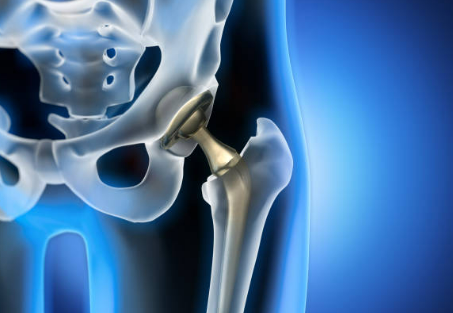

Si l'arthrose est évolué le traitement chirurgical et la prothèse de hanche vous sera proposé

Arthroplastie

Prothèse

Remplace l'articulation malade par une articulation métalique.